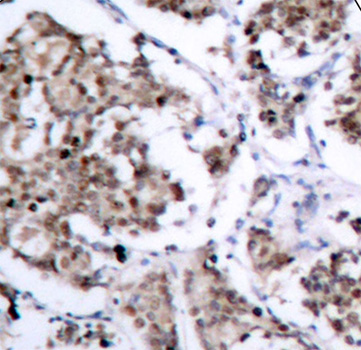

• AP0312: image 2

Immunohistochemical analysis of paraffin-embedded human breast carcinoma tissue using Phospho-Bad-S155 antibody.